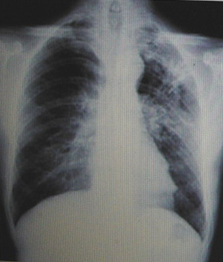

男性,23岁,午后低热2周。

A.左上肺炎

B.左上支气管扩张

C.左上浸润型肺结核

D.正常胸片

『正确答案』C